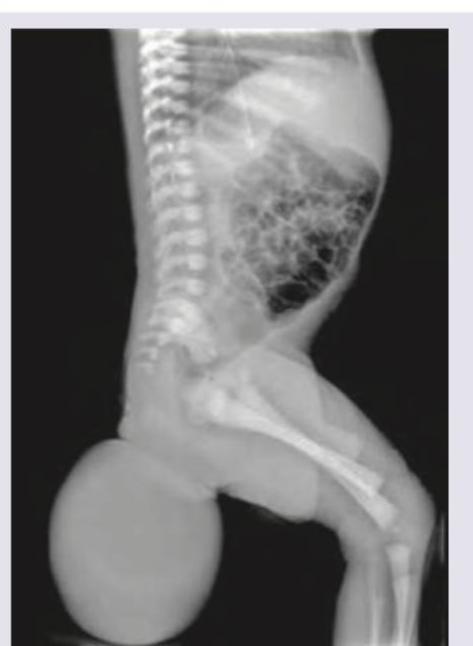

Infantogram shows presence of:

Explanation: ***Sacrococcygeal teratoma*** - The image shows a large, well-defined mass extending from the **sacrococcygeal region** of the infant. The presence of both soft tissue and calcifications within the mass (suggesting varying tissue types) is characteristic of a **teratoma**. - **Sacrococcygeal teratomas (SCTs)** are the most common germ cell tumors of childhood, typically presenting as external masses projecting from the lower back/buttocks. *Hemangioma* - A hemangioma is a **benign vascular tumor** that would typically appear as a soft tissue mass without the presence of internal calcifications or complex structures visible on plain radiography. - While they can be large, their radiological appearance would be primarily of **soft tissue density**, and they don't commonly arise with such distinct bony involvement or complex internal architecture. *Myelomeningocele* - A myelomeningocele is a form of **spina bifida** where the spinal cord and meninges protrude through a defect in the vertebral column, often presenting as a fluid-filled sac. - While it occurs in the same anatomical region, the image depicts a **solid, heterogeneous mass** with calcifications rather than a herniated neural tissue with cerebrospinal fluid. *Arnold-Chiari malformation* - Arnold-Chiari malformation is a structural defect in the **cerebellum**. - It involves the downward displacement of the cerebellar tonsils through the foramen magnum and would not present as an external mass in the sacrococcygeal region.